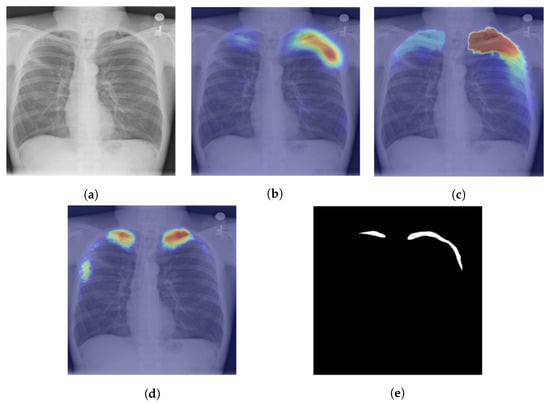

Figure 6.

The three steps proposed in [] for weakly supervised localization of tuberculosis manifestations in chest X-ray images with the red color representing areas where TB manifestation is highly likely: (a) chest X-ray image; (b) activation map generation with Grad-CAM++; (c) boundary improvements via IRNet; (d) segmentation; and (e) the ground truth where the pneumothorax manifested in the CXR.

The Grad-CAM was suggested in [,] to enable visual localization in determining the area afflicted by tuberculosis from chest X-ray pictures. The authors of [] say that they found saliency maps to be more successful than Grad-CAMs since tuberculosis manifests with small features. The Grad-CAM++ is used in [] for better and more accurate weakly supervised segmentation of tuberculosis from a chest X-ray. The Grad-CAM++ is used to create class activation maps; after that, the heatmaps are thresholded and then refined with a dense conditional random field (CRF) [] to improve the boundaries between various object classes. The author of the paper went beyond providing visual localization and created segmentation masks utilizing post-processing techniques like noise filtering, thresholding, and CRF, and an example of their finding is given in Figure 6.